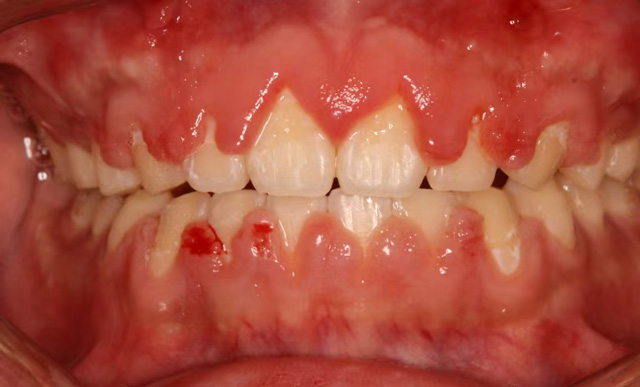

为了拥有整齐的牙齿和舒展的笑容,很多人选择了口腔正畸治疗。在与牙套亲密接触的过程中,有些人发现自己的牙龈变大变鼓了,按一按也不痛,还挺瓷实。这种情况被称为“牙龈增生”。

最常见的原因是第一个,口腔清洁做得不好。固定矫正治疗期间,由于托槽和弓丝容易挂住食物,需要在餐后做好刷牙等口腔清洁工作,如果清洁不到位,大量的食物残渣会留在牙齿和牙龈上,为细菌提供了温床,长期这样会引起牙龈炎,直至牙龈增生。

杨艳(副主任医师):牙龈增生主要发生在固定托槽矫正人群中。以我的个人经验,十年多前牙龈增生是比较多的,随着患者口腔清洁意识的提高,还有矫治器的更新换代,现在在成年人中已经不常见了,在儿童和青少年里发生得更多一些。

至于原因,一方面是因为儿童对刷牙方法掌握得不好,或是没有做到每次吃完东西都清洁牙龈,另一方面也和激素有关,处于生长发育期的青少年由于激素相对紊乱,更容易出现口腔内的感染。

杨艳(副主任医师):牙龈增生对于矫正治疗没有明显的影响,它主要是影响美观,特别严重的可能会影响到咀嚼。

轻度的牙龈增生,一般在拆除托槽后可以逐步恢复。如果矫正治疗尚未结束,我们除了给患者强调要好好刷牙以外,还会给予药物牙膏和涂抹外用药物进行消炎治疗,并根据需要进行龈上洁治(洁牙),龈下洁治(刮除龈下结石)。

对于增生达到一定程度的患者,可以通过切除增生部分来治疗。

有一点需要提醒大家,有些患者在矫正的初期会出现牙龈增生,随着治疗的推进,牙齿排列逐渐变得整齐,增生情况会有所好转。特别是牙齿拥挤错乱比较严重的患者,平时就不容易清洁干净,牙周情况不好,刚开始矫正时更容易发生增生。